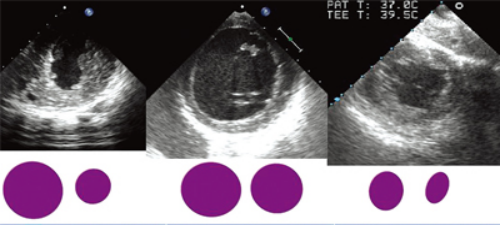

以左心室中段短轴切面为例(图7),在这个切面上,可以观察左、右心室的心腔大小,室壁厚度。左心室正常值男性55 mm,女性50 mm,正常情况下左心室和右心室横径的比例关系大约是5∶2;而左心室舒张末面积(LVEDA)和左心室收缩末面积(LVESA)的比例大致是2∶1。

TEE-Focus左心室舒缩异常的超声图像监测模式(图9,表4):

外周血管扩张模式(图9A)的特征是左房压正常,LVEDA正常,LVESA显著减小,差值增大,比值增大,室壁运动正常/增强;

心衰模式(图9B)的特征是左房压升高,LVESA与LVEDA均增大,差值减小,比值减小,室壁运动减低;

容量不足模式(图9C)的特征是左房压降低,LVESA与LVEDA均减小,差值减小,比值减小,室壁运动正常/增强。

图9经胃底左心室短轴切面用于心功能判断